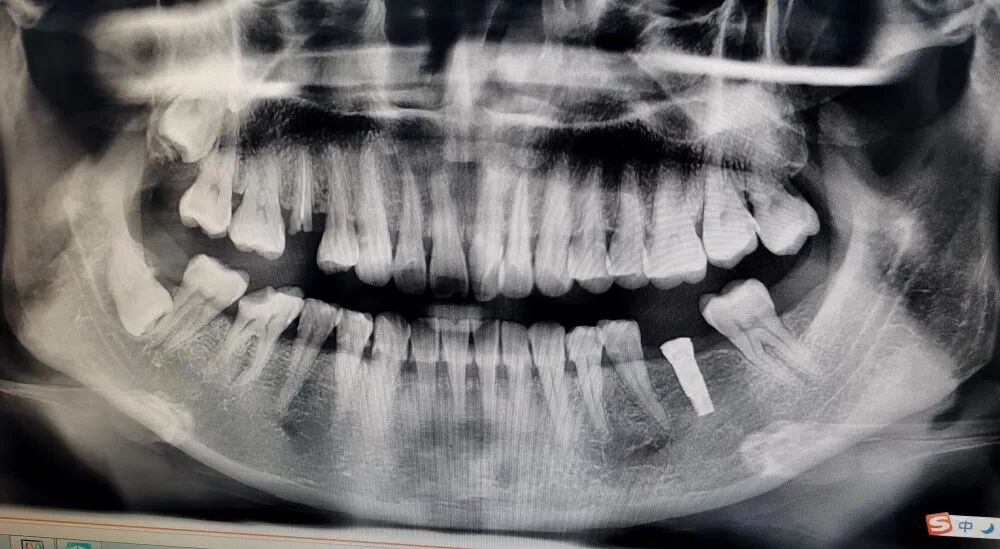

近日,顺庆区人民医院口腔科成功开展了六台种植牙手术,在全科人员的努力和配合下,为六位患者无痛精准地完成了植入手术,手术过程顺利,术后患者无不适感,效果满意,大大提升了患者的生活质量。

种植牙技术一直以不伤邻牙,仿生真牙的技术模式,一度成为缺牙修复的最佳修复方式,但因其高昂的价格让广大患者望而却步。近期,顺庆区人民医院口腔科特推出一款特惠种植牙,欧美的技术,民族的品牌,让“高大上”的种植牙,真正成为人人都能种的起的人类第三副牙齿!